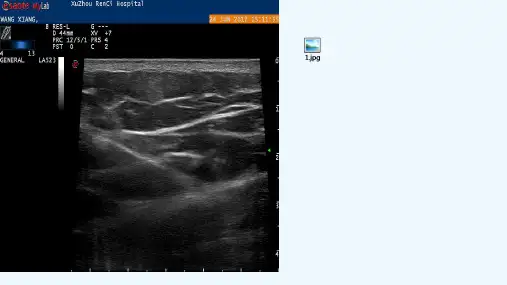

超声引导下注射皮质类固醇治疗狭窄性腱鞘炎的疗效摘要:目的:对超声引导下注射皮质类固醇治疗狭窄性腱鞘炎的临床疗效进行分析。

方法:将我院2017年6月至2018年6月收治狭窄性腱鞘炎患者作为此次研究对象,共计46例,患者在入组之后利用随机分组法分为两组,分别予以闭合穿刺法注射药物(对照组)与超声引导下注射皮质类固醇(实验组)进行治疗,对比两组患者治疗效果。

结果:实验组患者疼痛消失率86.9%与对照组患者疼消失率60.8%比较,差异具有统计学意义(P<0.05);实验组患者治疗总有效率95.6%与对照组患者治疗总有效率73.9%比较,差异具有统计学意义(P<0.05)。

结论:超声引导下注射皮质类固醇治疗狭窄性腱鞘炎具有操作简单、安全性高等优点,较好的缓解患者的疼痛症状,其疗效得到患者及临床的认可,在临床中有着广阔的应用前景。